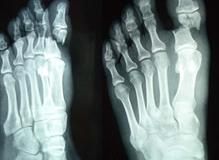

凡疑為骨折者應常規進行X線拍片檢查,可顯臨床上難以發現的不完全性骨折、深部的骨折、關節內骨折和小的撕脫性骨折等,即使臨床上已表現為明顯骨折者,X線拍片檢查也是必要的,可以幫助了解骨折的類型和具體情況,對治療具有指導意義。

骨折的X線檢查一般應拍攝包括鄰近一個關節在內的正、側位片,必要時須加攝斜位、切線位或健側相應部位的x光片。仔細閱讀x光片後應辨明以下幾點:

骨折大多數發生於足部距骨、跟骨、跖骨及趾骨部位。

距骨骨折後局部腫脹、疼痛、活動功能障礙,被動活動踝關節時距骨疼痛劇烈,明顯移位或脫位時則出現畸形。跟骨骨折時除足跟疼痛、腫脹、功能障礙外,可出現瘀血斑,多見於跟骨內側及足底。嚴重者足跟部橫徑增寬,足弓變平,足部變長。從高處墜下時,若衝擊力量大,足跟部先著地,脊柱前屈,引起脊椎壓縮性骨折或脫位,甚至衝擊力沿脊柱上傳,引起顱底骨折和顱腦損傷,所以診斷跟骨骨折時,應常規詢問和檢查脊柱和顱腦的情況。跖骨、趾骨骨折時前半足或趾骨部位腫脹、疼痛明顯。第5跖骨基底部撕脫骨折的診斷應與跖骨基底骨骺未閉合、腓骨長肌腱的籽骨相鑑別,後兩者壓痛腫脹不明顯,骨片光滑規則,且為雙側性。跖骨頸疲勞骨折最初為前足痛,勞累後加劇,休息後減輕,2~3周后在局部可摸到有骨隆凸。由於沒有明顯的暴力外傷史,易被誤診。

踝部與跗骨正側位x線照片,跟骨x線側位、軸位照片,跖、趾前半足正、斜位x線片可以明確距骨、跟骨、跖骨及趾骨骨折的移位程度、類型以及有無合併其他骨折脫位。